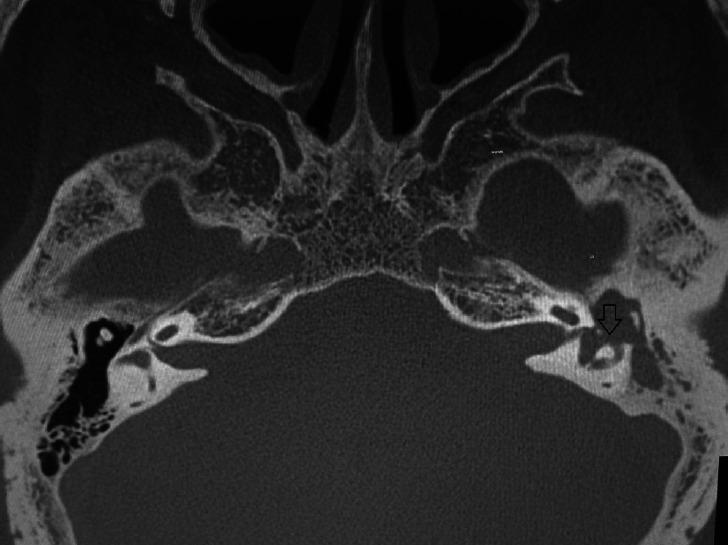

Cholesteatoma is a cystic non tumorous lesion of the temporal bone that has the ability to destroy nearby structures by its power to cause bone resorption and as a result, fatal complications prevail. We aimed to conduct a comprehensive review for pathogenesis of acquired cholesteatoma, bone resorption mechanisms, and offer a future vision of this serious disease. We have reviewed different theories for pathogenesis of acquired cholesteatoma including the most relevant and updated ones with special emphasis on the mechanisms of bone resorption through Medline/PubMed research using the keywords 'aetiopathogenesis, bone resorption, acquired cholesteatoma, temporal bone, and cytokines.' In order to strengthen our study, we searched the reference lists of identified reviews. Cholesteatoma is a subject of debate among otolaryngologists since it was prescribed firstly. Over many decades, several theories were postulated for aetiopathogenesis of cholesteatoma with a tendency to follow more than one theory to explain the proper nature of that disease. Until now, the mechanism of bone resorption has yet to be more clarified. In the last century, a leap has occurred in the field of biomolecular cholesteatoma research which improved our knowledge about its pathophysiology and bone destructive mechanism. However, surgery is still the only available treatment. We conclude that discovery of new therapeutic choices for cholesteatoma other than surgery by the use of anti-growth, anti-proliferative, apoptotic agents as well as medications that antagonize osteoclastogenesis should be the main concern in the future clinical and experimental research work. Also, searching for predictors of the aggressiveness of cholesteatoma can affect the timing of intervention and prevent occurrence of complications.

胆脂瘤是颞骨的一种囊性非肿瘤性病变,它能够通过引起骨质吸收的能力破坏附近结构,因此会出现致命并发症。我们旨在对获得性胆脂瘤的发病机制、骨质吸收机制进行全面综述,并对这种严重疾病提出未来展望。我们通过使用关键词“病因发病机制、骨质吸收、获得性胆脂瘤、颞骨和细胞因子”在医学在线/医学期刊数据库(Medline/PubMed)中进行检索,对获得性胆脂瘤发病机制的不同理论进行了综述,包括最相关和最新的理论,并特别强调了骨质吸收机制。为了加强我们的研究,我们搜索了已识别综述的参考文献列表。自首次被描述以来,胆脂瘤一直是耳鼻喉科医生争论的话题。在过去几十年里,针对胆脂瘤的病因发病机制提出了几种理论,并且倾向于采用多种理论来解释该疾病的本质。直到现在,骨质吸收的机制仍有待进一步阐明。在上个世纪,生物分子胆脂瘤研究领域取得了飞跃,这增进了我们对其病理生理学和骨质破坏机制的了解。然而,手术仍然是唯一可用的治疗方法。我们得出结论,未来临床和实验研究工作的主要关注点应该是通过使用抗生长、抗增殖、凋亡药物以及拮抗破骨细胞生成的药物来发现除手术之外的胆脂瘤新治疗选择。此外,寻找胆脂瘤侵袭性的预测指标可以影响干预时机并预防并发症的发生。